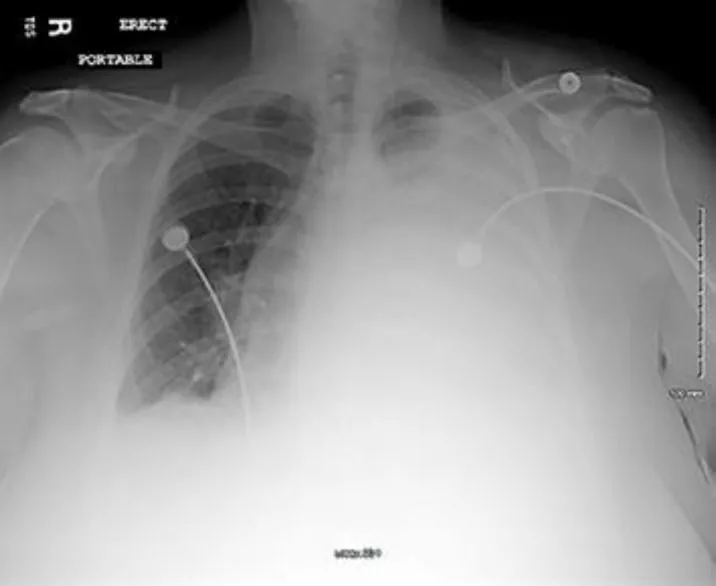

Еще через месяц женщина снова была госпитализирована с жалобами на одышку и боли в грудной клетке слева. Симптомы возникли через 2 недели после выписки из стационара. При рентгенографии (рис. 2) и РКТ органов грудной клетки обнаружен гидроторакс слева с явлениями ателектаза левого легкого. При повторной РКТ органов грудной брюшной полости отмечено увеличение периспленической гематомы до 8 × 8 × 6 см. С целью разрешения гидроторакса и ателектаза выполнено дренирование плевральной полости. В общей сложности удалено 1,35 л серозной жидкости соломенного цвета. По анализу выпота — экссудат. Через 4 суток пациентка была выписана, в течение 1 года наблюдения ее состояние не ухудшилось.

image003.jpg

Рисунок 2 [1].